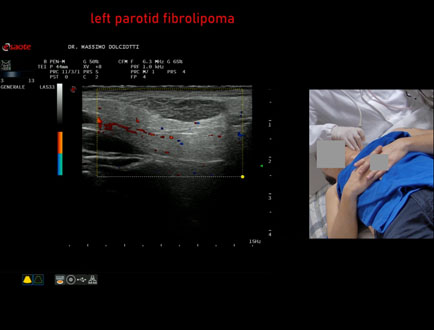

Data inserimento: 09/01/2026

Ecografia del: 22/12/2025

Strumento: Esaote MyLab Eight

Sonda: Lineare Multifrequenza 3-13 MHz

Età Paziente: M 56 anni

Motivazione dell'esame: da alcuni mesi tumefazione parotidea sinistra non dolente.

Commento all'esame: le immagini ed il video documentano formazione iso-ipoecogena, a margini definiti ma irregolari, delle dimensioni di 26 x 7 mm, senza evidenza di vascolarizzazione intra nodulare, da ricondurre, come prima ipotesi, a fibrolipoma, ma meritevole di approfondimento diagnostico.

Conclusioni: fibrolipoma parotideo sinistro (left parotid fibrolipoma).